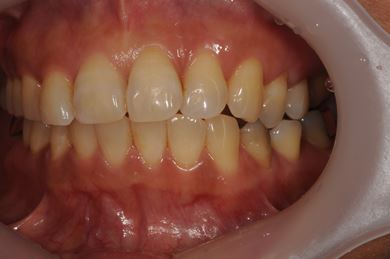

インプラントの症例写真 IMPLANT

骨再生インプラント治療+セラミック治療+歯肉歯槽骨整形

| 性別/年齢 | 女性 / 42歳 | ||||||||||||||||||||||||||||||||

| 主訴 | インプラント治療を受けたい。 | ||||||||||||||||||||||||||||||||

| 治療方針 | 左上奥欠損部分をインプラント治療にて機能的・審美的回復を行う。 | ||||||||||||||||||||||||||||||||

| 治療内容 | インプラント2本(ソケットリフト)、メタルボンドセラミック3本(メタルボンド用土台1本)、歯肉歯槽骨整形 | ||||||||||||||||||||||||||||||||

| 総治療費 | 1,227,713円 | ||||||||||||||||||||||||||||||||

| 治療期間 | 11ヶ月 |